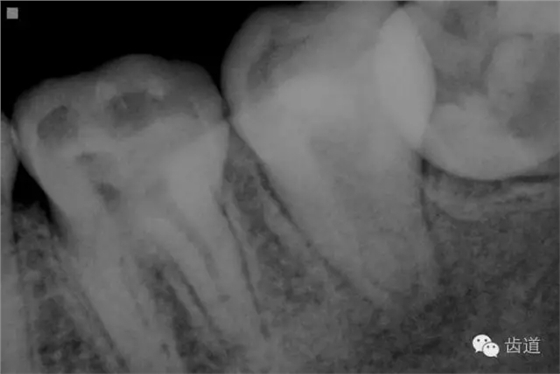

2. 術(shù)前X片

可見(jiàn)37根管影像清晰,根中上三分之二粗大,根尖三分一分為近遠(yuǎn)中兩根管,形態(tài)均呈弧形,根尖周膜連續(xù)性中斷,根尖周透射影明顯

17. X線主尖片